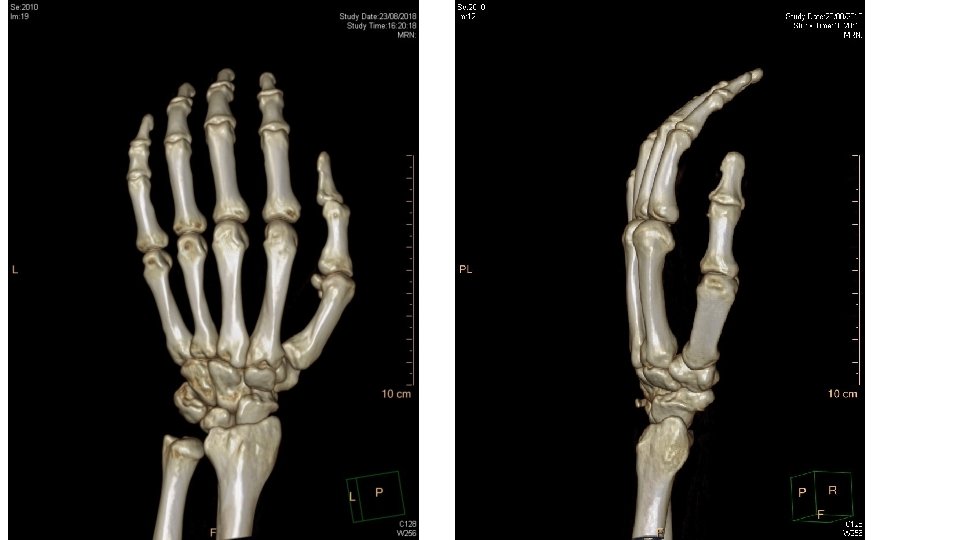

Q 2 • A 55 years old gentleman presented to AED due to fall with out stretched left hand. He complained left wrist pain and decreased range of movement over the left wrist. Physical examination showed tenderness along the ulnar border of the left wrist. X-ray of the left wrist was taken.

• What is the x-ray finding? And what is the diagnosis? • What is the mechanism of injury? • What is the indication for surgical intervention? Give 4. • What is the non-surgical management?

Avulsion fracture of triquetrum • Lateral view of the wrist x-ray • Small radiodense fragment just dorsal to the proximal row of carpal bones • Mechanism of injury • Typically occur from a fall onto an outstretched arm with the wrist in extension and ulnar deviation, or in extreme flexion • Avulsion fracture, usually off the dorsal radial surface account up to 93% of triquetrum # • Indication for surgery • • Open # Comminuted # Asso. nerve injury (ulnar n. ) Asso. vascular injury • Non-surgical management • Immobilization with short arm cast with the wrist placed in slight extension and the MCP joints free for 3 -6/52